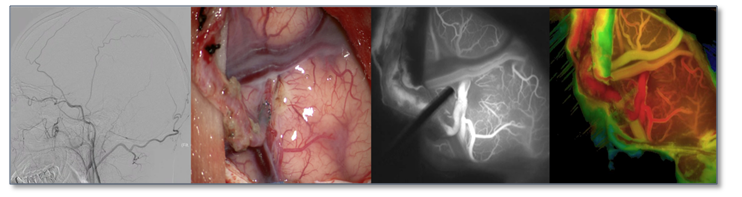

我科自2012年开始建立脑血管亚专业组,亚专业带头人为段永红主任医师,2022年聘请北京天坛医院介入中心刘爱华主任为客座教授。团队主要成员为蒋园丁、何健,每年开展脑动脉瘤、脑血管畸形、烟雾病、动静脉瘘、脑缺血等疾病手术量270台次以上,脑出血病例治疗量达900例,影响力覆盖周边省市。2022年获批出血性脑血管疾病衡阳市重点实验室,取得多个省级重点科研项目资助。

目前脑血管外科亚专业组的诊治水平在全国与全省都处于领先地位,湖南省首家开展锁孔入路动脉瘤夹闭术,能常规开展几乎所有复杂疑难脑血管疾病手术,如多模态监测下开展颅内复杂动脉瘤夹闭术、内镜联合显微镜治疗复杂动脉瘤,杂交手术治疗巨大脑血管畸形等。其中儿童脑动静脉畸形破裂急性期的一期切除术,技术处于全国领先地位,曾经在全国开展多次学术交流活动。

随着技术的进步,介入微创治疗成为脑血管疾病的重要手段,科室能常规开展所有脑血管疾病的介入治疗,包括复杂颅内动脉瘤的介入治疗、硬脑膜动静脉瘘的介入手术、覆膜支架植入、血流导向装置植入手术等代表神经介入前沿水平的高难度手术。